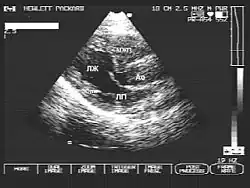

- Эхокардиография — основной метод диагностики. Позволяет оценить выраженность и локализацию гипертрофии, степень обструкции, нарушения диастолической функции и т. д.